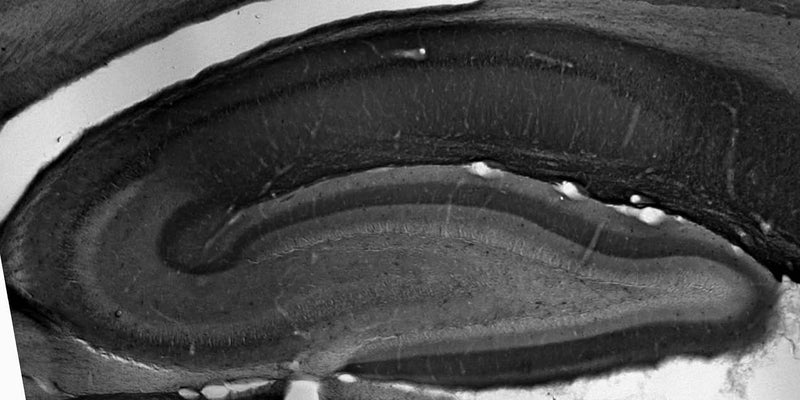

| 35076711 | 1:50 | Chaudhary, R., et al. 2022. Modulation of pacemaker channel function in a model of thalamocortical hyperexcitability by demyelination and cytokines. Cerebral Cortex, 4397-4421. |